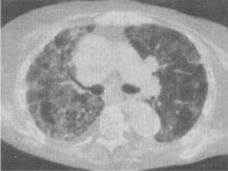

患者,女,45岁,气急,咳嗽,胸痛,手、足关节痛,关节肿胀,结合CT图像,最可能的诊断是()。

A、肺癌

B、特发性肺间质纤维化

C、系统性红斑狼疮

D、硬皮病

E、类风湿肺病

E